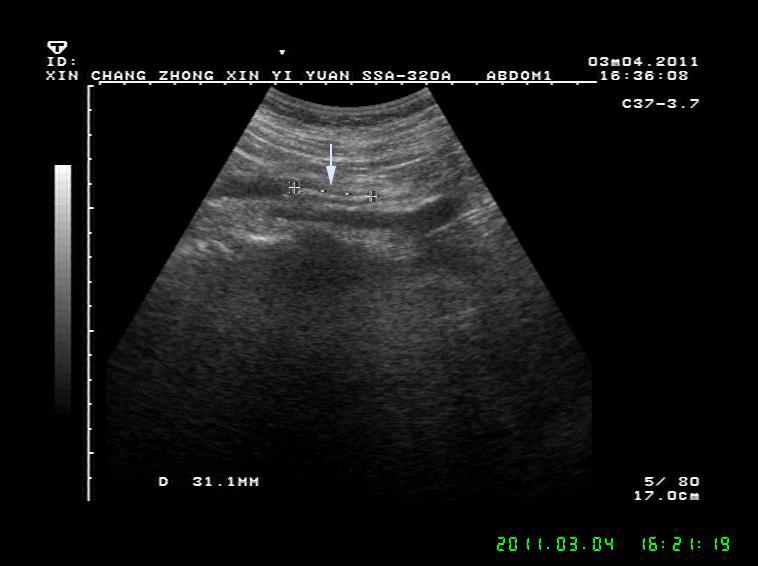

泌尿系结石

夏季到了,急诊室内面色苍白,捂着肚子,额头沁满汗珠的患者越来越多了,见到医生的第一句就是“医生,我的结石又痛了!” 泌尿系结石是一种常见病,多发病,医学上把肾脏结石、输尿管结石、膀胱结石和尿道结石统称为尿路结石。男性发病率明显高于女性。 01 尿路结石常见的病因 1.个体因素和遗传因素。 2.长期在高温环境中工作,机体水份蒸发多,尿液浓缩,容易形成结石。 3.代谢性疾病,如甲状旁腺功能亢进,尿中钙盐增多;痛风病人尿中尿酸盐增加,均易得结石。 4.某些食物或药物的长期作用使尿液酸碱度改变,也是结石生成的一种诱因。 5.前列腺增生或其他原因引起的排尿不畅,慢性尿潴留,因尿液浓缩尿液中盐份容易沉积,形成结石。 6.长期卧床,因骨质脱钙,血钙浓度增加易致结石形成。 结石的诱发因素多种多样,因此结石的预防也要有针对性。结石成分的分析有助于明确病因。盲目忌口对预防结石收效不明显。这里顺带一句,很多病人误认为柿子吃多了会得尿路结石,实际上这是一种讹传,柿子吃多了可能会凝结成胃肠道柿石,而与泌尿系结石完全没有关系。 02 泌尿系结石发作时的症状和体征 泌尿系结石原发部位一般都在肾脏内,平时不会有什么感觉,只有等结石掉入到肾盂出口处或输尿管内,引起输尿管梗阻和痉挛时才会出现一系列症状和体征。输尿管结石常停留于上端、下端及髂血管旁三个生理性狭窄处,结石对管壁的摩擦和刺激,可导致输尿管局部粘膜损伤、水肿甚至并发炎症。 结石疼痛常常呈突发性,表现为一侧腰部或腹部刀绞样疼痛,多数疼痛剧烈难忍,部分病人疼痛可放射至腹股沟区或会阴部。可伴有恶心呕吐、血尿,尿频、尿急、尿痛及反射性少尿。 体征表现为面色苍白,痛苦病容以及腰痛特有的姿势,检查可有肾区叩击痛。少数输尿管结石病人可以长期没有明显症状,往往要等到健康检查时才发现。 泌尿系结石的诊断:泌尿系统结石诊断并不难,一般通过超声或CT检查就能明确结石的大小和部位,肾输尿管有无扩张、积水。尿检有无红细胞可作为参考依据。 肾结石 肾积水 输尿管结石 膀胱结石 03 泌尿系统结石的治疗 1. 肾脏结石比较大的,或数量较多的,或伴有积水的可考虑外科微创或手术治疗。肾结石较小的一般没有症状也不影响肾脏功能,可不作处理。 2.输尿管结石不管在哪个部位,基本上都有不同程度的输尿管扩张和肾脏积水,时间久了积水可能会加重,影响肾脏功能。因此输尿管结石一经确诊一定要尽早治疗。0.5--0.6cm及以下的结石如果疼痛不是很厉害可以选择药物排石,但切记要间隔一星期左右复查,直到结石排出。较大的结石或保守治疗不能排出的结石可首先考虑体外冲击波碎石治疗。 3.膀胱结石最大径在3cm以下且前列腺增生不明显的可考虑体外碎石治疗。结石过大,或前列腺增生显著的可选择钬激光治疗或膀胱切开取石。 泌尿系结石虽然不算什么大病,但发作时疼痛是最剧烈的,大多需要急诊处理。体外冲击波碎石具有简便快捷,疗效确切,安全性高、痛苦较小、费用合理等优势,病人普遍容易接受,可以作为治疗泌尿系结石的首选。少数病人碎石后结石仍无法排出,或者是结石被包裹的病人则需要泌尿外科进一步处理。 输尿管结石碎石后呈长条状 敲黑板啦——预防结石有妙招●● 1.养成多饮水的习惯。多饮水可稀释尿液,降低尿内各种盐类的浓度。水源的改善对结石的预防也有一定的意义。 2.尽早除去尿路梗阻因素,如前列腺增生症、尿道狭窄等。 3.积极、规范、彻底治疗泌尿系的感染性疾病。 4.长期卧床的病人,应鼓励多活动,勤翻身,减少骨质脱钙。 5.有甲状旁腺机能亢进者,应积极治疗。